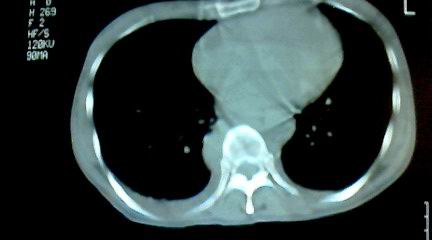

标题: CT25218:请教!胸部CT,胸8椎体骨质破坏,伴周围软组织肿。 [打印本页]

标题: CT25218:请教!胸部CT,胸8椎体骨质破坏,伴周围软组织肿。

患者,女41岁,肢体乏力。

两肺上叶继发性肺结核;胸椎结核并椎旁寒性脓肿形成。

胸椎结核并椎旁寒性脓肿形成。

两肺上叶继发性肺结核;胸椎结核并椎旁寒性脓肿形成